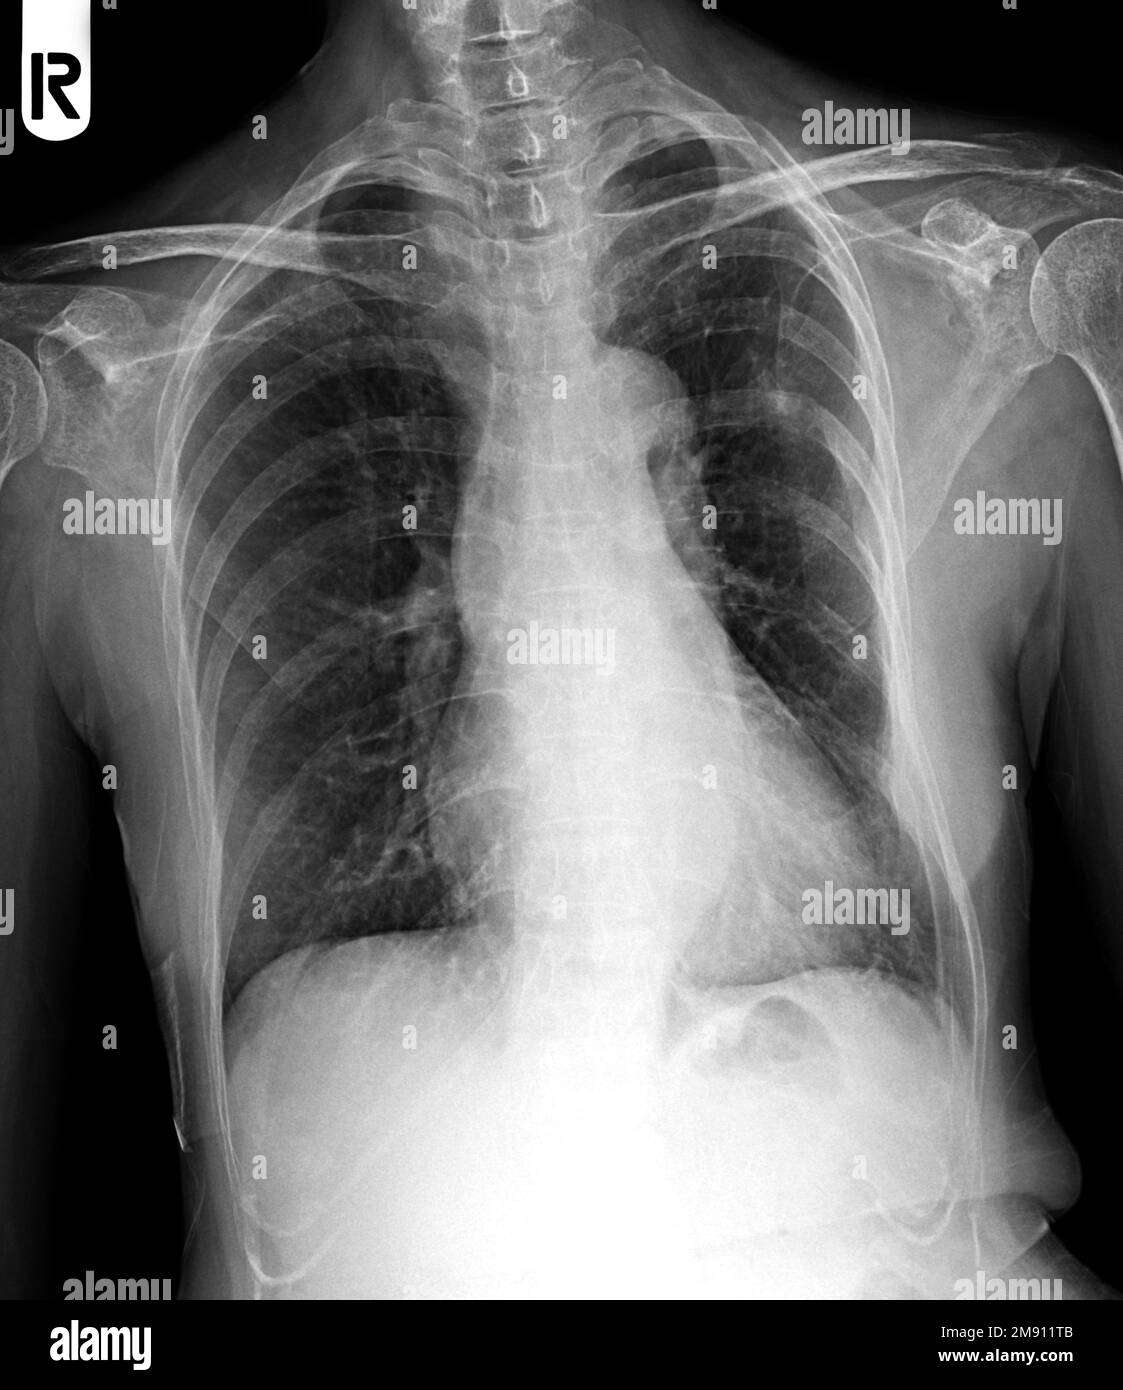

From ar.inspiredpencil.com

Chest X Ray Tb Vs Normal What Does A Chest X-Ray Show If You Have Tb This may show signs of cavitation, pleural effusion, mediastinal or hilar lymphadenopathy, or parenchymal infiltrates,. If you have symptoms of tuberculosis (tb), tests you may have include: Your health care provider will do other tests to determine if you have inactive tb or active tb. A positive test result for tb infection means you have tb germs in your body.. What Does A Chest X-Ray Show If You Have Tb.